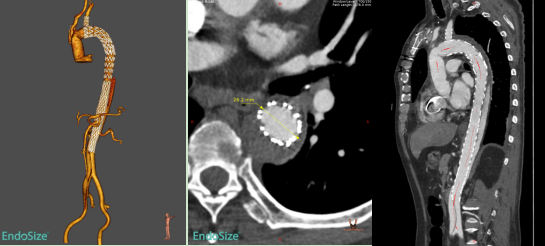

本次入组患者为60岁男性,1个多月前因急性Stanford A型主动脉夹层在我院接受“主动脉瓣交界悬吊+升主动脉及全弓置换+降主动脉象鼻支架置入+三尖瓣成形术”。术后1个月复查CTA提示:象鼻支架以远残余夹层,且夹层累及胸降主动脉、腹主动脉、右侧髂总及髂外动脉,真腔狭窄,假腔大,胸腹主动脉多发夹层破口,胸段肋间动脉以假腔供血为主。

术前CTA

术前,胡佳主任医师团队对患者病情进行了详尽的术前评估和反复讨论,经过精细影像学分析和手术模拟推演,制定了个体化手术治疗方案。术中,患者全麻后采用左侧股动脉穿刺建立通路,主动脉造影证实象鼻支架以远残余夹层真腔狭窄,存在多发内膜破口。手术选用近端直径30mm、远端直径24mm、长度290mm的A型夹层全腔内重建系统,其中覆膜段长度为120mm。支架近端锚定于象鼻支架内,远端锚定于肾下腹主动脉。手术过程顺利流畅,术后即刻造影显示胸段残余夹层近端破口有效覆盖,近端假腔不再显影,远端真腔扩张良好,手术治疗效果达到预期。

术后复查CTA进一步证实,患者残余夹层覆膜支架段内膜破口有效覆盖,假腔无血流,远端真腔扩张良好。

术后复查的CTA